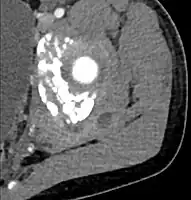

CT with IV contrast showing enlargement and heterogeneous hypodensity in the right pectoralis major muscle. A focal abscess collection with gas within it is present medially. There are enlarged axillary lymph nodes and some extension into the right hemithorax. Note the soft tissue and phlegmon surrounding the right internal mammary artery and vein. The patient was HIV+ and the pyomyositis is believed to be due to direct inoculation of the muscle related to parenteral drug abuse. The patient admitted to being a "pocket shooter"- CT exam showing a multiloculated fluid collection in the left gluteus minimus muscle found to be a staph aureus pyomyositis in a 12-year-old healthy boy.